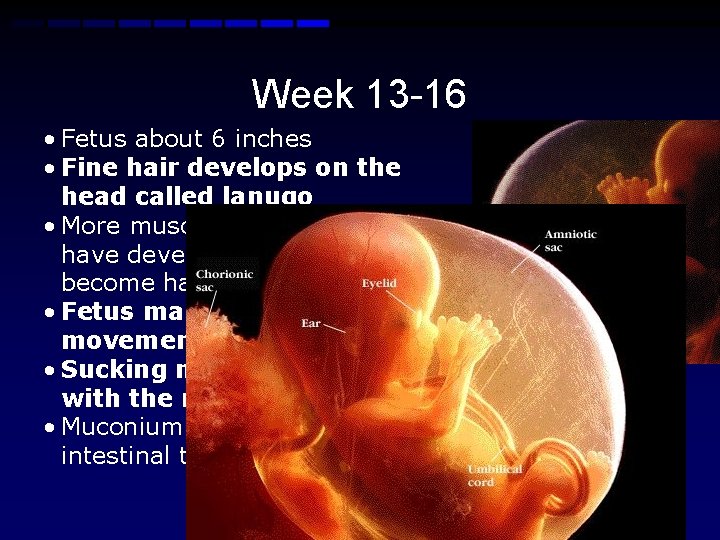

Week 13 -16 • Fetus about 6 inches • Fine hair develops on the head called lanugo • More muscle tissue and bones have developed, and the bones become harder • Fetus makes active movements • Sucking motions are made with the mouth • Muconium is made in the intestinal tract